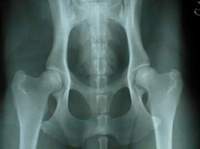

Röntgenfoto’s van normale heupen

Röntgenfoto’s van HD-heupen

Bij rassen die gevoelig zijn voor heupdysplasie is het gewoonte om de fokdieren aan een röntgenonderzoek te onderwerpen. Daarna wordt uitspraak gedaan over de ernst van de afwijking en dus ook over de kans op nakomelingen met soortgelijke problemen. Een verantwoorde koper stelt zich hiervan op de hoogte.

Heupdysplasie uit zich in eerste instantie in een afwijkende manier van bewegen van de achterbenen. Dan is er nog geen sprake van pijn. Deze fase treedt al in het eerste levensjaar van de hond op. Door röntgenfoto’s te laten nemen komt de eigenaar meer te weten over de aard en de ernst van de aandoening.